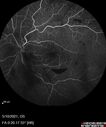

Elevated Episcleral Venous Pressure and Retinal Hemorrhages in both eyes284 views78 year old female with chronic red eye. The eyes are red all the time now. She is on Xeralto because of a history of blood clots in her lungs (2005 about). She has not had problems since. She has had floaters for many years. Ever since her eyes got funny she sees more floaters in both eyes. She had a brain scan over 6 months ago which was OK. She also had double vision when this first started which went away. She could not drive for a few months.

VA OD: Dcc20/32-1

VA OS: Dcc20/125

IOP: TP: OD:17 OS:16

Neuroimaging did not show a CC fistulaJul 13, 2021